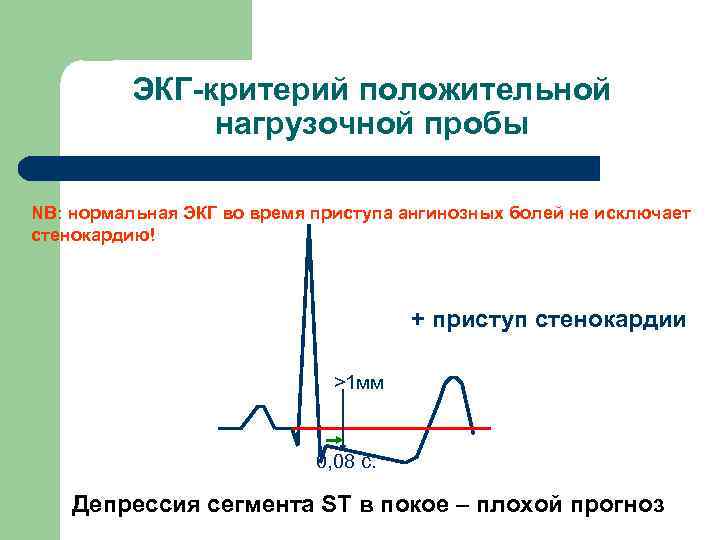

ЭКГ-критерий положительной нагрузочной пробы NB: нормальная ЭКГ во время приступа ангинозных болей не исключает стенокардию! + приступ стенокардии >1 мм 0, 08 с. Депрессия сегмента ST в покое – плохой прогноз